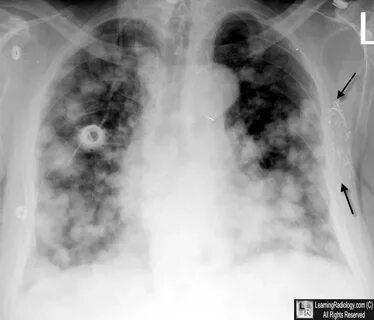

Kirli hava akciğer kanseri sebebi

Türk Kanser Araştırma ve Savaş Kurumu Derneği Genel Başkanı Prof. Dr. Tezer Kutluk, hava kirliliğinin, Avrupa'da tüm kanserlerin yüzde 1'inden, tüm kanser ölümlerinin ise yüzde 2'sinden sorumlu olduğunu, akciğer kanserinde ise hava kirliliğinin rolünün yüzde 9'a çıktığını söyledi.